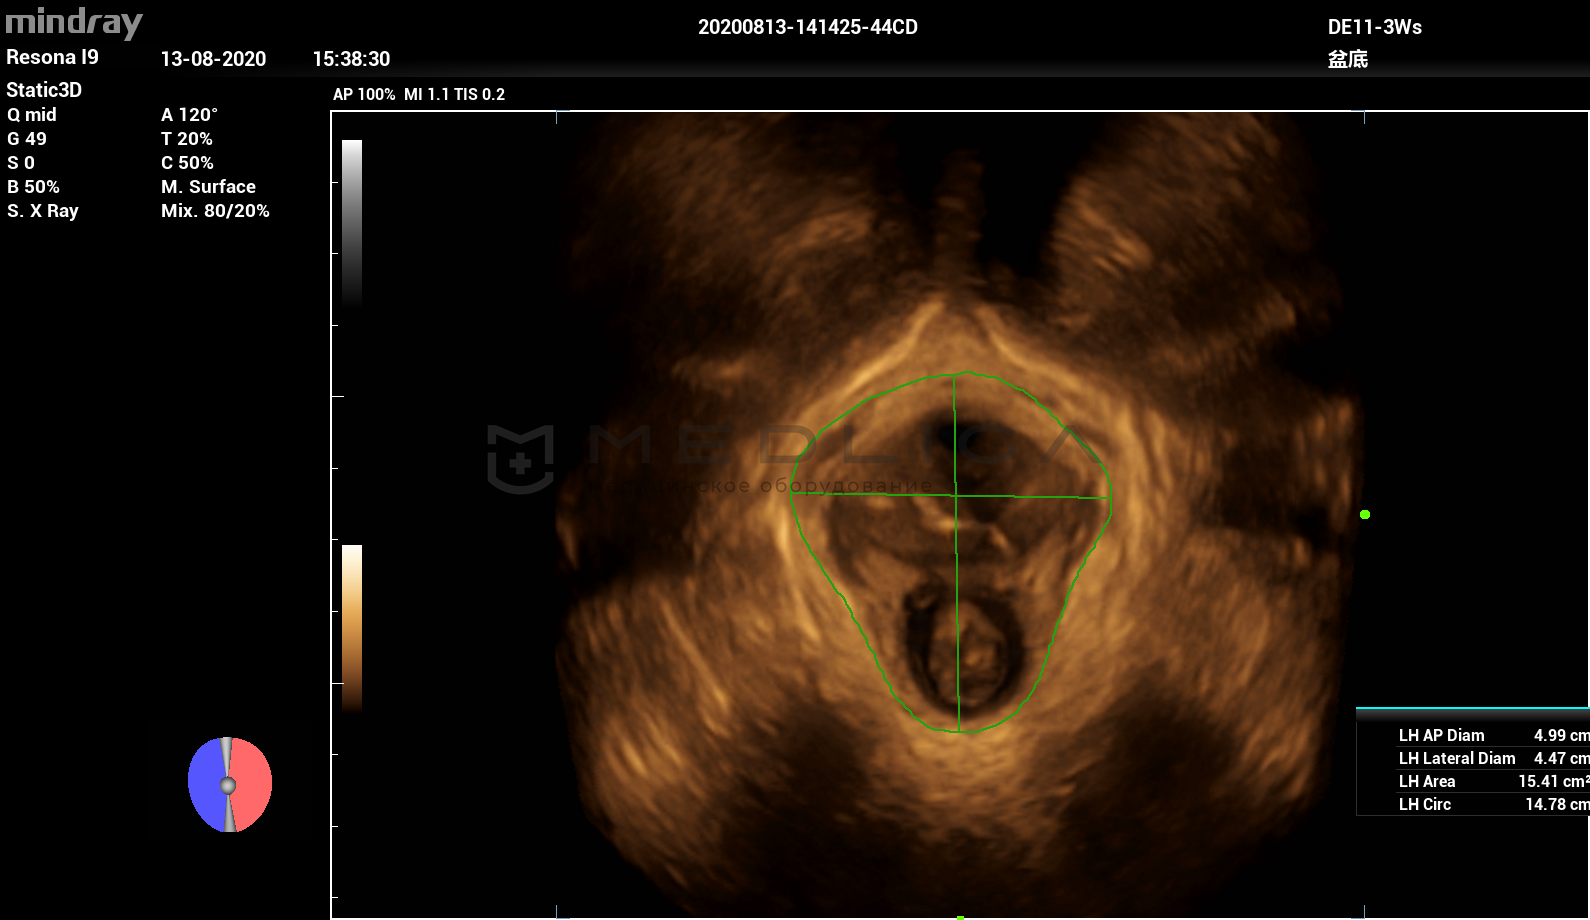

Smart Pelvic - новое решение, позволяющее значительно упростить диагностическую процедуру и свести к минимуму время исследования функций мышц тазового дна. Благодаря чрезвычайно простому пользовательскому интерфейсу, программа генерирует стандартную систему координат и автоматически просчитывает все связанные измерения в течение нескольких секунд.